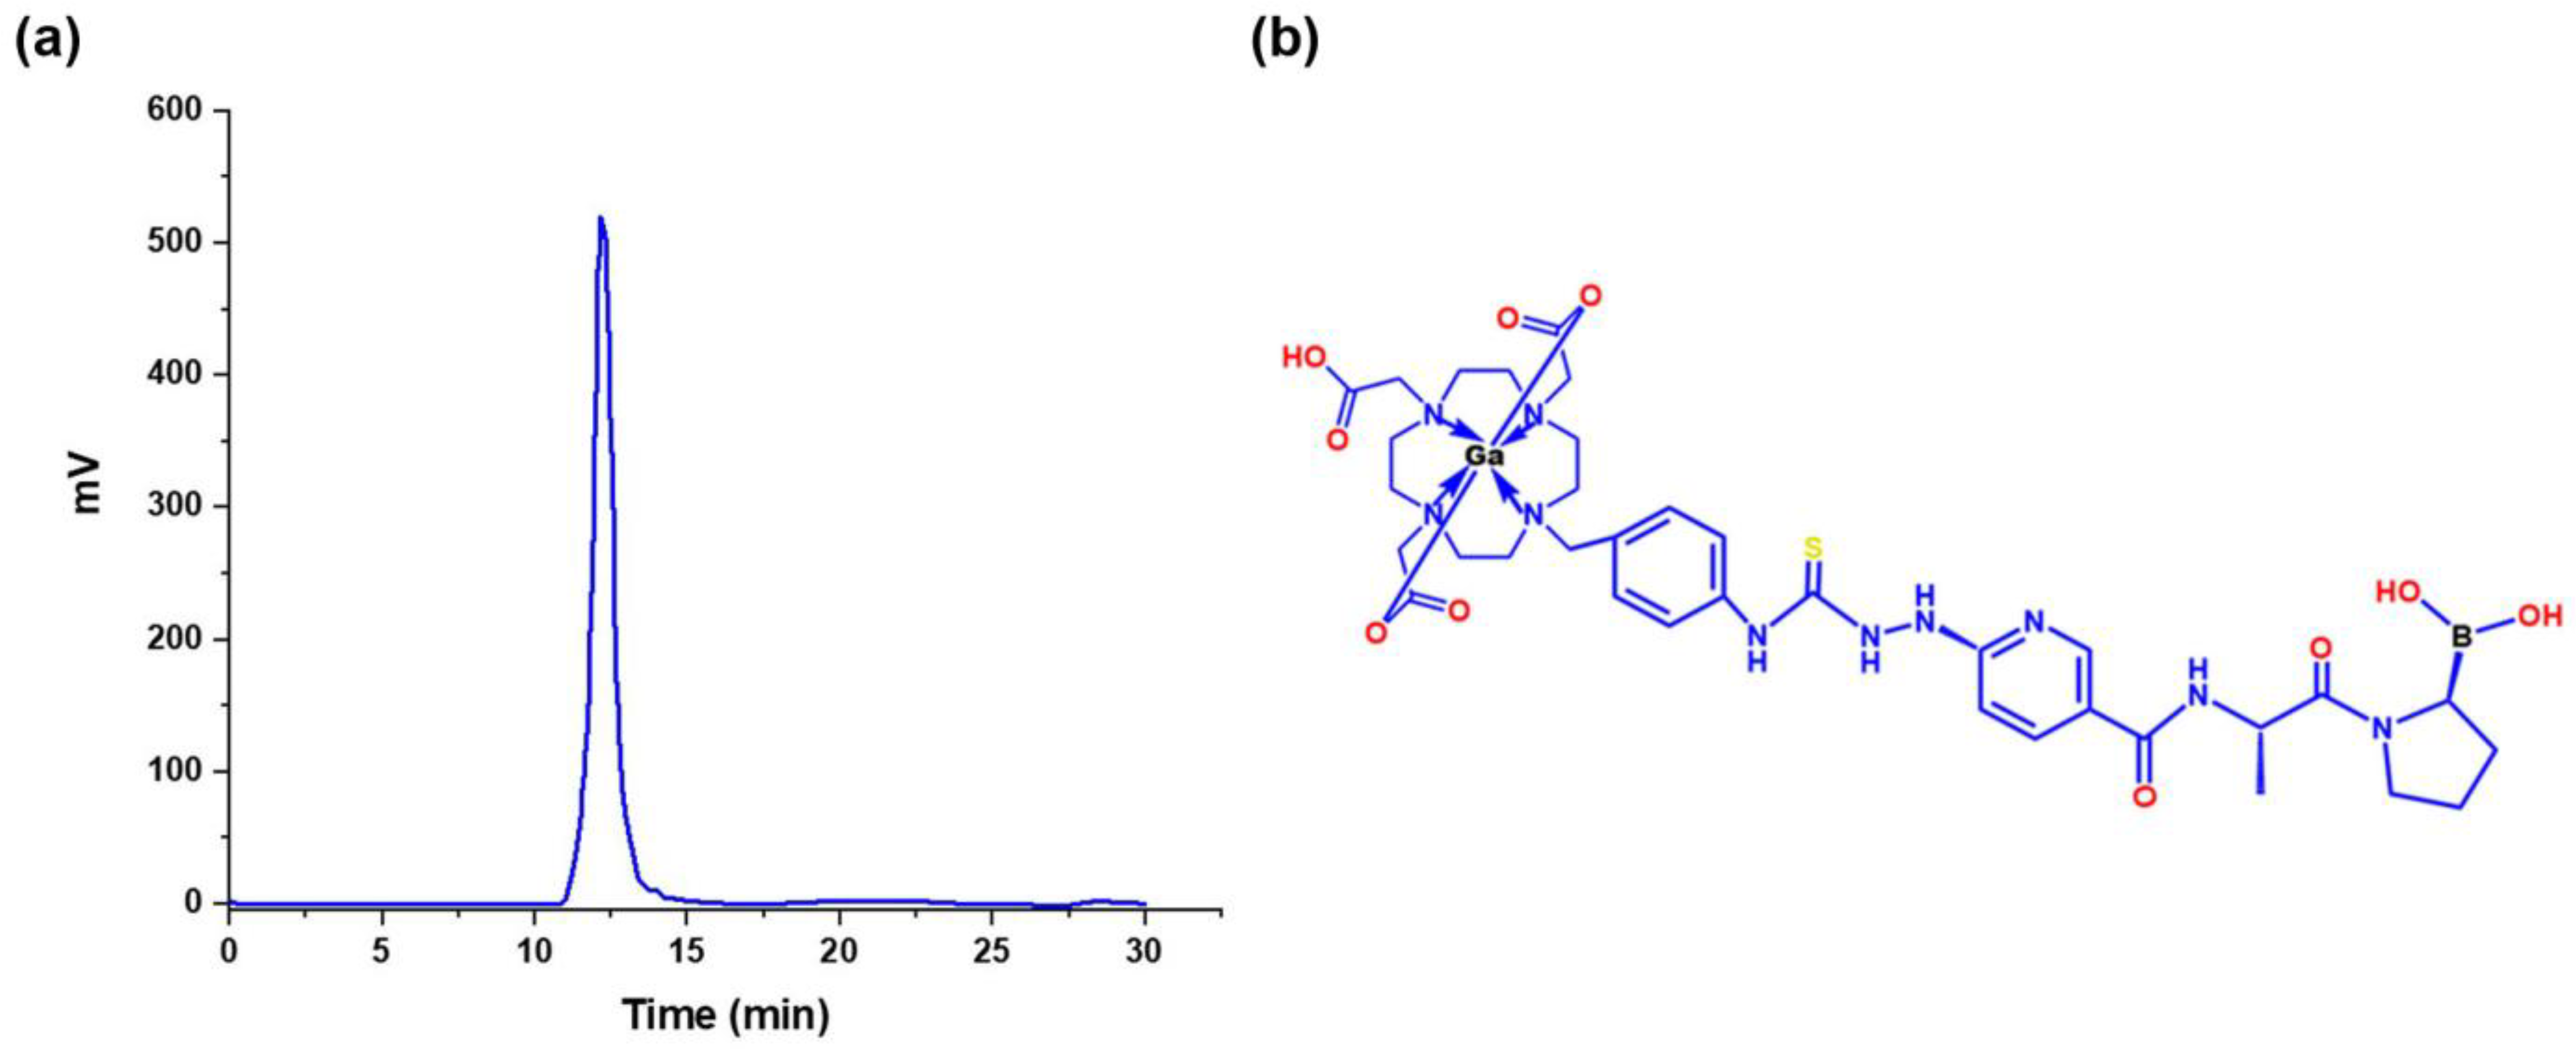

3.3.2. 68Ga-iFAP Radiochemical Purity

3.2. Chemical Synthesis